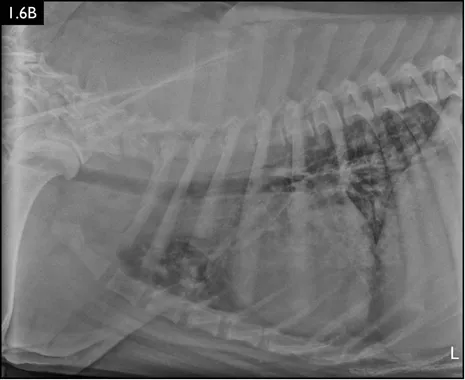

Clinical signs can be strongly suggestive of bacterial pneumonia, but radiographs are important for confirmation, to characterize the disease (and potential etiology) and to provide a baseline for monitoring response to treatment (Figs. 1.4–1.6). A lag between clinical signs and radiographic changes can occur, and initial radiographs may be normal or appear discordant with clinical severity.

Fig. 1.6A–D Radiographs of a dog with suspected aspiration pneumonia. A diffuse alveolar pulm...